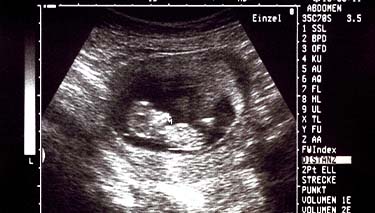

The ultrasound will pick up images of your baby's organs in a series of cross sections. This can be confusing at first, until you become used to the images and your eyes adjust. Your baby's bones will be white on the screen and the amniotic fluid will appear as black. Their tissues will be grey and have a speckled appearance.

- Measurements of your baby's head, biparietal diameter, length and a measurement of their femur (long bone in the thigh) will also be taken. These measurements are compared with the average for babies of the same gestation.